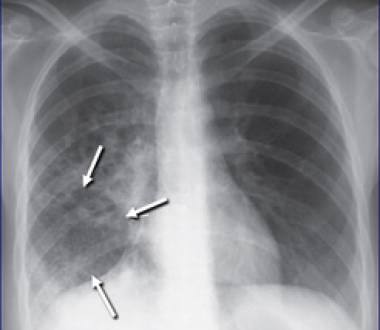

One of Dr. Ojha’s projects is based upon the hypothesis that the extraordinary persistence of M. tuberculosis against antibiotics is facilitated by the pathogen’s ability to grow in organized, multicellular structures called biofilms. His laboratory has developed various molecular tools to visualize the location of drug tolerant “persisters” inside the biofilms, and using these tools, is asking how, over time, localization and concentration of these “persisters” can be perturbed.